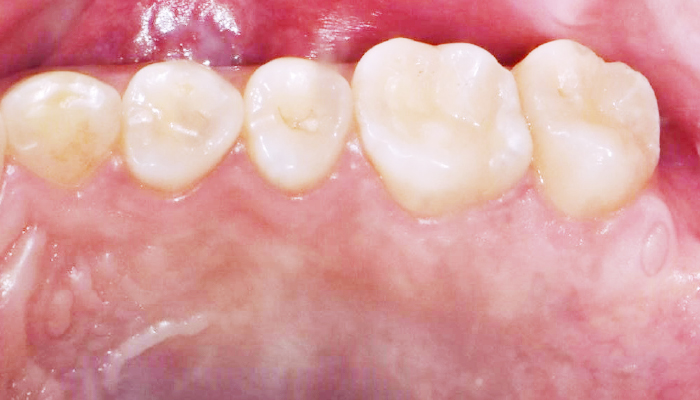

이갈이는 다양한 원인에 의해 발생되는 것으로 치아의 마모, 턱관절 통증, 두통 등을 유발합니다. 치과치료와 함께 생활습관을 교정하는 방법으로 이갈이를 줄여나갈 수 있습니다.

다양한 합병증을 동반하는 이갈이